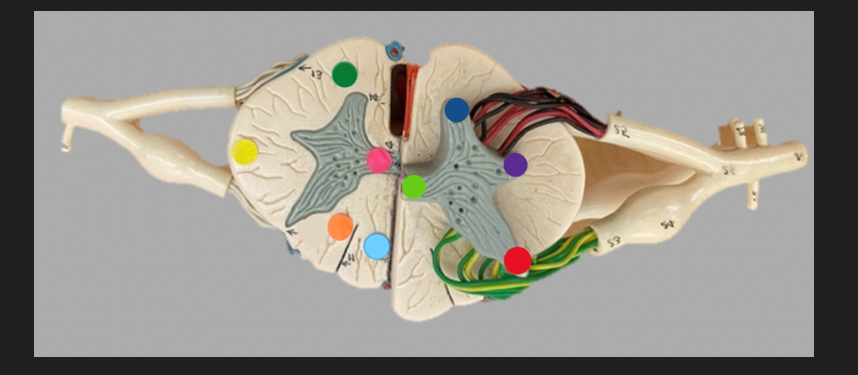

green dot

spinal nerve

orange dot

ventral root

pink dot

dorsal root

blue dot

dorsal root ganglion

red dot

dorsal ramus

yellow dot

ventral ramus

purple dot

anterior median fissure

red dot

posterior (dorsal) horn

purple dot

lateral horn

dark blue dot

anterior (ventral) horn

orange dot

dorsal column

yellow dot

lateral column

dark green

anterior column

line green and pink doit

gray commissure

light blue dot

posterior median sulcus